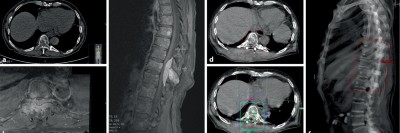

Ein 48-jähriger Patient berichtet von belastungsabhängigen Schmerzen in den Beinen seit mittlerweile zehn Jahren. Bildgebende Untersuchungen der Hals- und Lendenwirbelsäule konnten die claudicatioartigen Beschwerden bislang nicht erklären. Eine lange überfällige MRT des Thorakalbereichs führt schließlich zur richtigen Diagnose.

Chilaiditi-Syndrom in einer CT-Aufnahme/© Peters F & Ritz J-P/ all rights reserved Springer Medizin Verlag GmbH, Initial potenziell instabile Läsion von BWK 10 bei Multiplem Myelom/© Kaufmann, J., Schmidberger, H. / all rights reserved Springer Medizin Verlag GmbH, Springer Medizin Podcast - Endometriose/© (M) Willer D. et al. / all rights reserved Springer Medizin Verlag GmbH Logo: Springer Medizin Verlag GmbH, Zentrale Lungenembolie/© Springer Verlag Berlin Heidelberg 2015, Volumetrie des Bulbus olfactorius/© Keweloh S.. et al. doi.org/10.1007/s00106-025-01650-z unter CC-BY 4.0, Gebrochener Fuß im Gips/© Aleksandr Kirillov / stock.adobe.com (Symbolbild mit Fotomodell), CT-Pulmonalisangiographie/© Das M et al. doi.org/10.1007/s00117-016-0100-3 unter CC-BY 4.0, Kanüle für Katheterbehandlung/© romaset / stock.adobe.com, Komplexe, offene Fraktur des Ellenbogens vom Grad 2/© Springer Medizin Verlag GmbH, Mann erhält einen CT-Scan /© Mark Kostich / stock.adobe.com (Symbolbild mit Fotomodell), Verschlussazoospermie bei unilateraler zystischer Alteration der Samenblase und kontralateraler Samenblasenagenesie/© Wittler C et al, Indikationen zur konventionellen Bildgebung am Ellenbogen/© Rentschler V et al. / all rights reserved Springer Medizin Verlag GmbH, Person schenkt Bier in Kolben/© Parilov / Stock.adobe.com (Symbolbild mit Fotomodell), Neoadjuvanten Strahlentherapie bei Liposarkom/© Podleska, L.E. et al. / all rights reserved Springer Medizin Verlag GmbH, Frau erhält eine Strahlentherapie/© Mark Kostich / stock.adobe.com (Symbolbild mit Fotomodell), Schaumiges Bronchialsekret bei akutem Lungenödem/© Eichner M. doi.org/10.1007/s00063-025-01258-9 unter CC-BY 4.0, Bildgebung bei akuter Organblutung/© Nadjiri J / all rights reserved Springer Medizin Verlag GmbH, Bildgebung bei Beckenfraktur mit Blutung der A. iliaca interna/© Fink CB et al. / all rights reserved Springer Medizin Verlag GmbH, Traumatische Aortenverletzung/© Maier J et al. / all rights reserved Springer Medizin Verlag GmbH, Oberbauchsonoraphie/© C. Raschka, Muzinöses Prostatakarzinom/© Garzaro JRR et al. / all rights reserved Springer Medizin Verlag GmbH, Intraspinales thorakales Lipom/© Andreas Frank / all rights reserved Springer Medizin Verlag GmbH, Frau bei Strahlentherapie/© (M) Mark Kostich / Stock.adobe.com (Symbolbild mit Fotomodellen), Search Icon, Frau hält sich eine Brustseite nach Mastektomie/© chotiga / Stock.adobe.com (Symbolbild mit Fotomodell), Radiologin richtet Mammographiescreening ein/© LIGHTFIELD STUDIOS / stock.adobe.com (Symbolbild mit Fotomodellen)